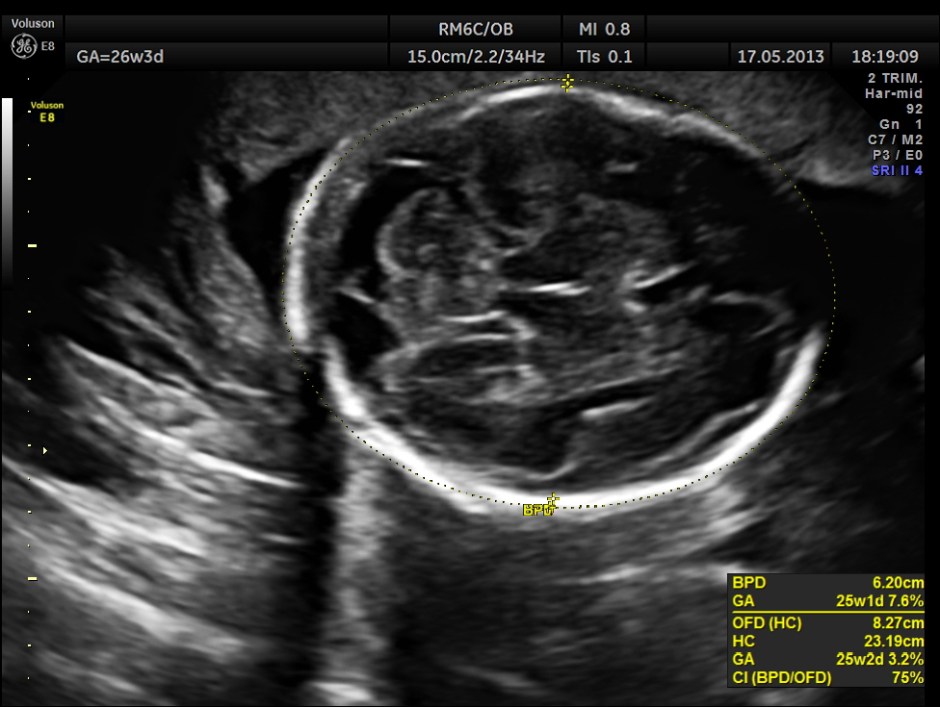

This was a 20 year old primi gravida on treatment for long standing seizure disorder ; she was on tab carbamazepine 200 mgm twice daily for a long time . The scan was done around 26 weeks of gestation.

The images are given below.

Cerebellum appears relatively smaller and corresponds to a GA of 22 to 23 weeks. Usually the cerebellum corresponds very closely to the GA and would be very useful to follow in cases of IUGR.

Cerebellum was < 2.3 %tile , suggestive of possible cerebellar hypoplasia. Unfortunately this patient was lost for follow up .